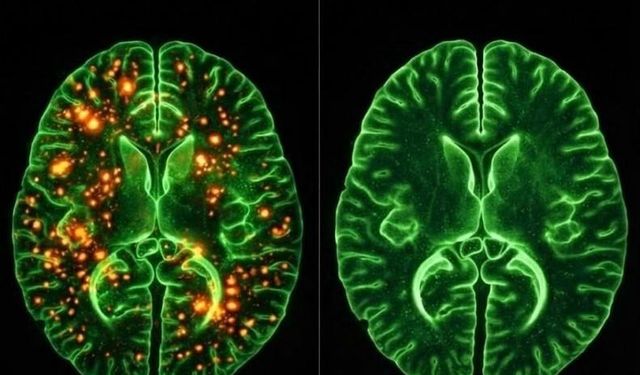

Varis şikayetleri arttı